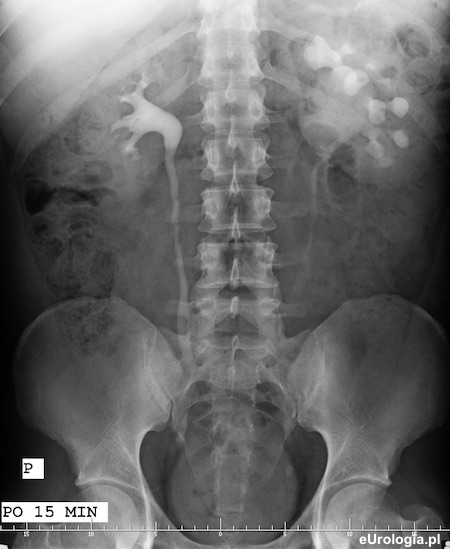

Zdjęcie urograficzne po 15 minutach od dożylnego podania środka kontrastowego. Widoczne układy kielichowo-miedniczkowe obu nerek i górne odcinki obu moczowodów. Obraz UKM lewej nerki sugeruje zwężenie połaczenia miedniczkowo-moczowodowego lub naczynie dodatkowe nerki.